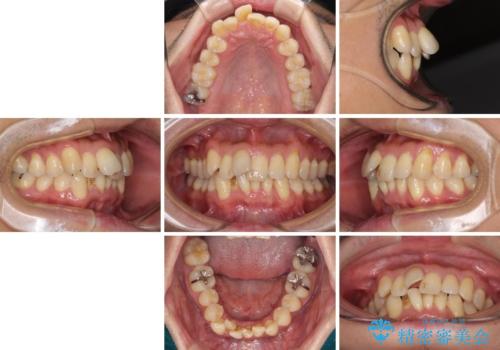

- 前歯のデコボコを気にして来院された患者様です。

インビザラインまたはワイヤー装置、どちらでも対応可能でしたが、自己管理の少なさ、期間の短さから、ワイヤー装置による矯正治療を行うこととしました。

治療開始の頃は、食事や歯磨きが慣れず、装置が頻繁に脱落しましたが、2,3ヶ月ほどで慣れ、その後は1年ほどで治療を終えることができました。